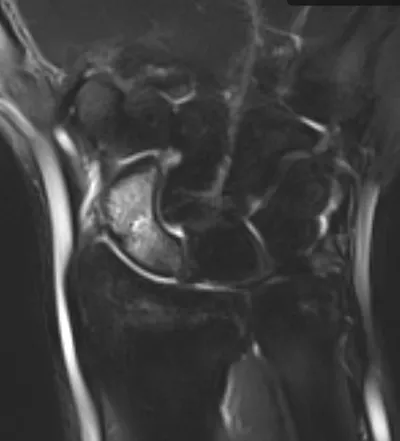

This collection contains 1 radiology images related to scaphoid, including various imaging modalities such as X-rays, MRIs, CT scans, and ultrasound images commonly used in medical diagnosis and education.